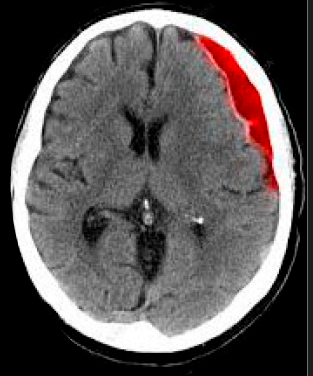

22

Q

¿Qué hematoma es este?

A

Epidural

21

¿Cómo se ve el hematoma epidural en TC?

• Biconvexo o lenticular

• Fx

• Importante Efecto de masa y herniación